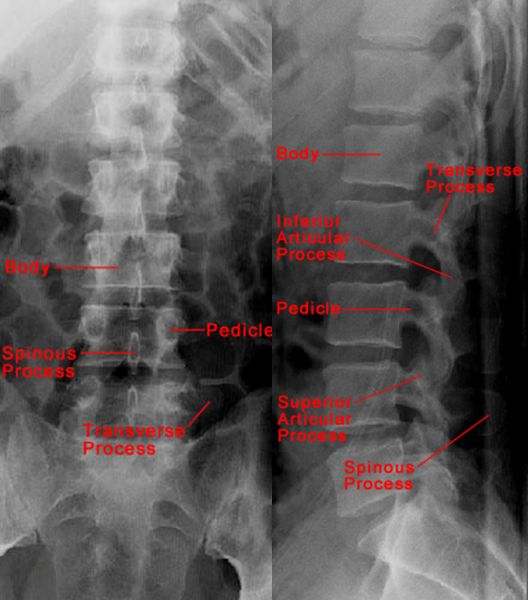

正常腰椎